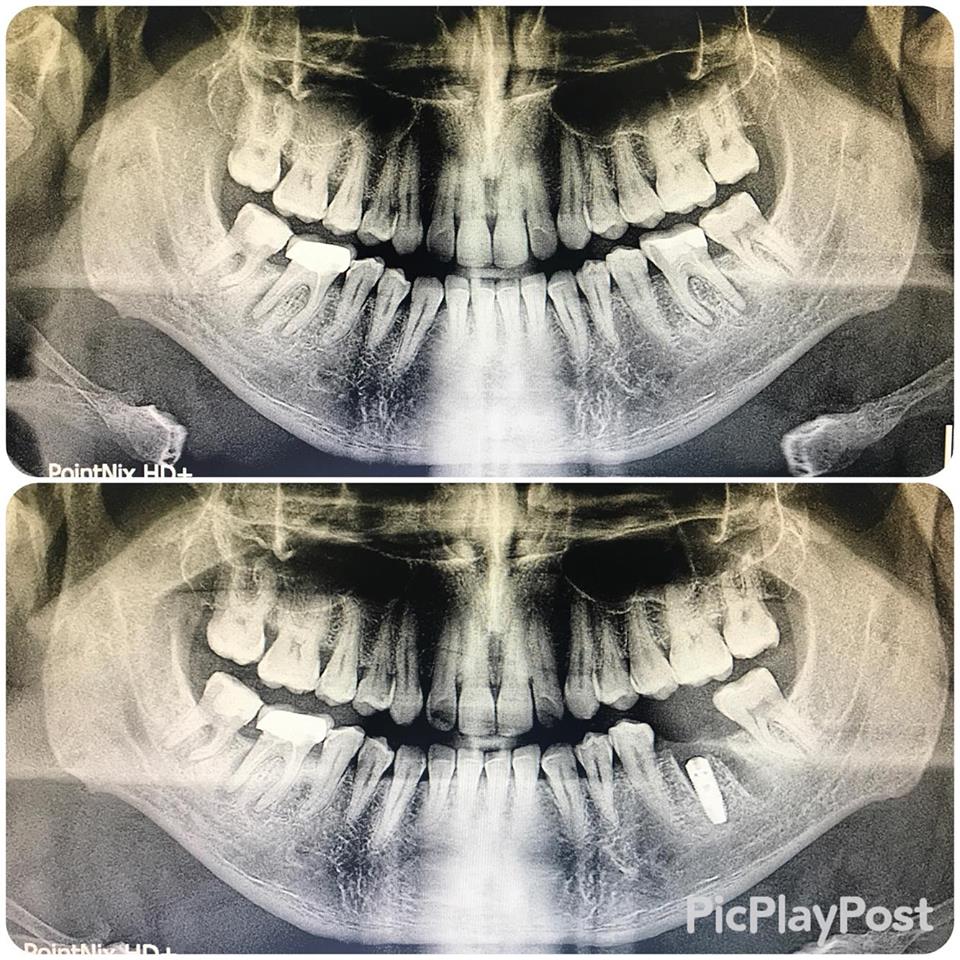

İMPLANT TEDAVİSİ

implant tedavisi